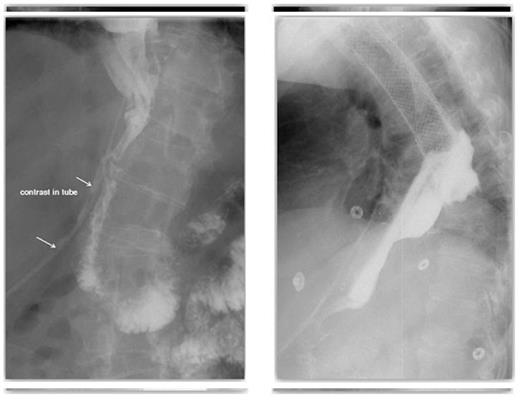

On post-operative day 7 a routine post-operative contrast swallow was performed. This identified a spill of contrast due to a 5mm anterior defect at the level of the oesophago-gastric anastomosis suggestive of focal ischaemia. This was managed with washout and drainage and a covered oesophageal stent. A further contrast swallow revealed contrast aggregating around the drain (Figure 1) and that the covered oesophageal stent was appropriately positioned with no evidence of on-going leak (Figure 2).

A contrast swallow demonstrating contrast aggregating around the drain & A covered oesophageal stent appropriately positioned with no evidence of leak